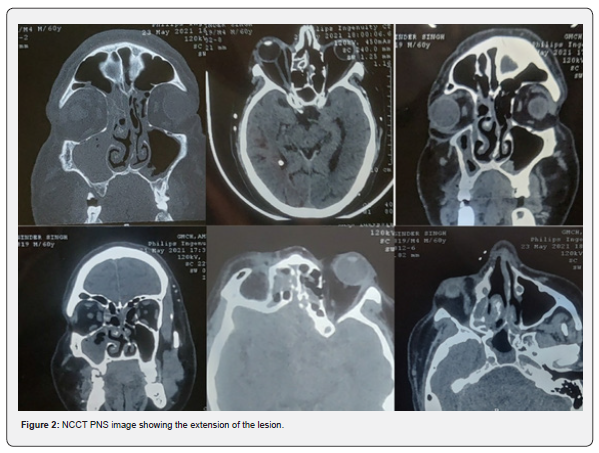

He was managed for Covid-19 as per the existing treatment protocol. After 10 days, he developed swelling and pain in the right eye along with right sided headache. On clinical examination, there was soft peri-orbital swelling with discoloration, proptosis and chemosis of the right eyeball. Nasal crusting along with nasal obstruction on right side. NCCT of Paranasal Sinuses (PNS) was done, which revealed features suggestive of fungal sinusitis- circumferential mucosal thickening with interspersed hyperdensities in bilateral paranasal sinuses (right>left) with bulky right medial rectus muscle and retrobulbar streakiness along with proptosis of right globe and inferior turbinate hypertrophy.